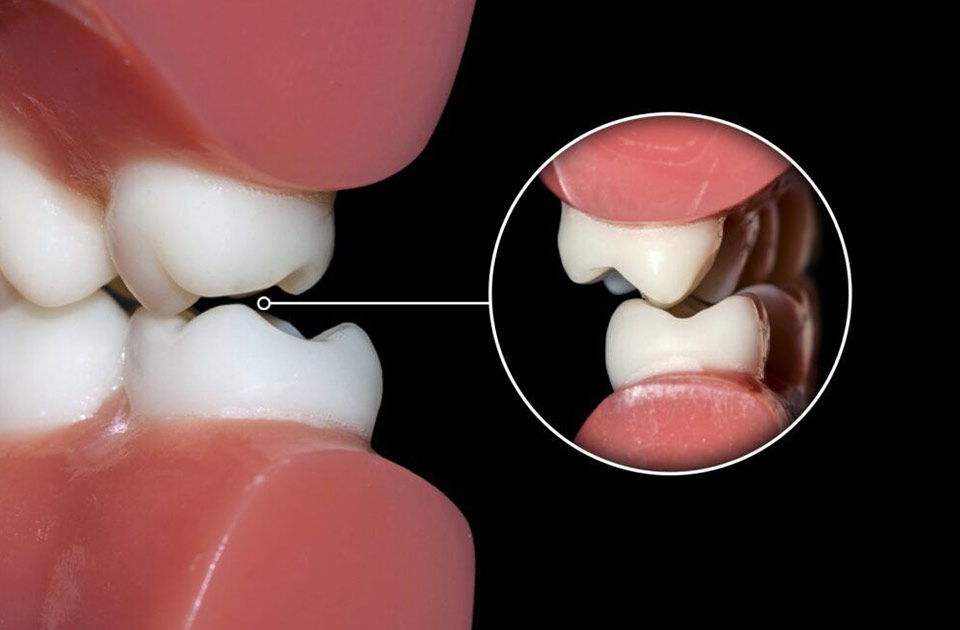

شاید شما هم جزو افرادی باشید که از کوتاه بودن دندان خود و فرسایش آن ها به یکدیگر احساس ناخوشایندی نداشته باشید معمولا دندان قروچه یا سایش دندان ها روی یکدیگر در خواب اتفاق می افتد و بدون اینکه فرد مورد نظر متوجه باشد دندان های آن دچار سایش هایی می شود اما امروز درباره علائمی با شما صحبت خواهیم کرد که متوجه بشوید دندان قروچه در خواب چه علائمی دارد و آیا می توان آن را درمان کرد یا خیر .

شاید تا به حال این نام را کم شنیده باشید اما دندان قروچه به معنی سایش دندان ها و فشردن فک بر روی هم می باشد که اغلب در خواب این اتفاق برای افراد می افتد و بر اساس پاسخ طبیعی به استرس و ناامیدی این اتفاق ممکن است رخ بدهد . به دلیل اینکه دندان قروچه در خواب رخ می دهد بسیاری از افراد از این اتفاق بی اطلاع هستند که در ادامه به علائم دندان قروچه در خواب می پردازیم

· قرار نگرفتن صحیح دندان ها روی هم

3 تراز کردن سطوح دندان یا جراحی کرونوپلاستی

اگر که علت دندان قروچه شما سطوح دندانی ناهموار باشد این روش موثر می باشد زمانی که سطوح دندان ها یکسان هستند وسوسه شما برای ساییدن دندان ها نیز کمتر می باشد .